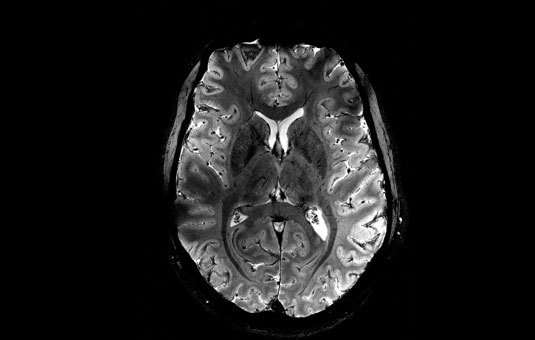

En un estreno mundial, los investigadores de la Comisión de Energía Atómica (CEA) de Francia revelaron este martes una serie de imágenes 'in vivo' del cerebro humano, adquiridas con la máquina de resonancia magnética más poderosa del mundo. La Iseult, que cuenta con un inigualable campo magnético de 11,7 teslas y fue construida en un esfuerzo de dos décadas, ha captado el cerebro vivo con una claridad sin precedentes.

Las más notables imágenes anatómicas del cerebro nunca antes obtenidas se tomaron en apenas cuatro minutos. Los expertos señalan que su resolución es impresionante para un lapso temporal de adquisición tan corto. Se logró una resolución en el plano de 0,2 mm y grosor de corte de 1 mm, lo que representa un volumen equivalente a unos pocos miles de neuronas.

En comparación, la misma calidad de imagen requeriría horas con los escáneres de resonancia magnética actualmente disponibles (de 1,5 o 3 teslas). Esto no es realista en la práctica, ya que los pacientes no se sentirían cómodos y cualquier movimiento haría que la imagen se vea "borrosa".